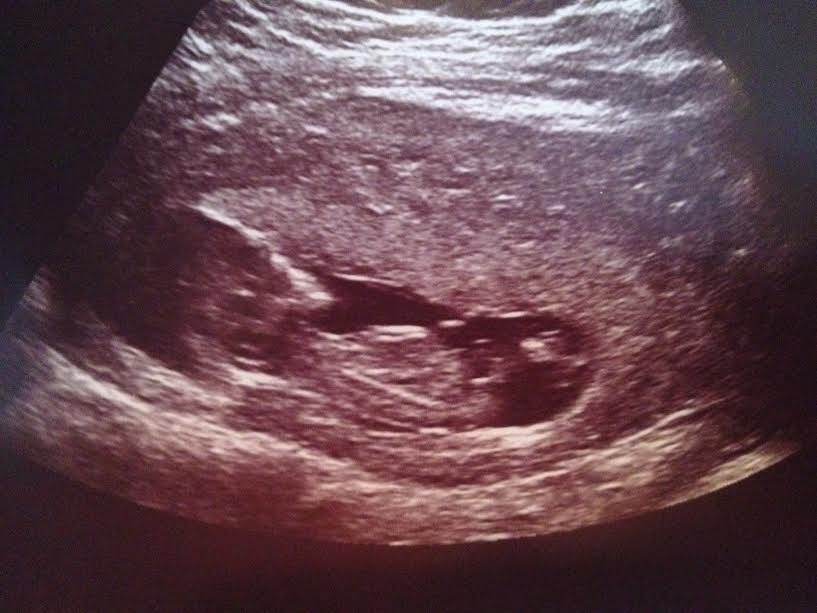

Here is my scan image from GA 12w1d but baby measured a few days ahead at 12w5d CRL *I think*. I say I think because it's not listed on my scan image and I remember seeing this date on the screen with CRL during the scan but now I'm second guessing myself because it's been weeks.

Attachment 34787